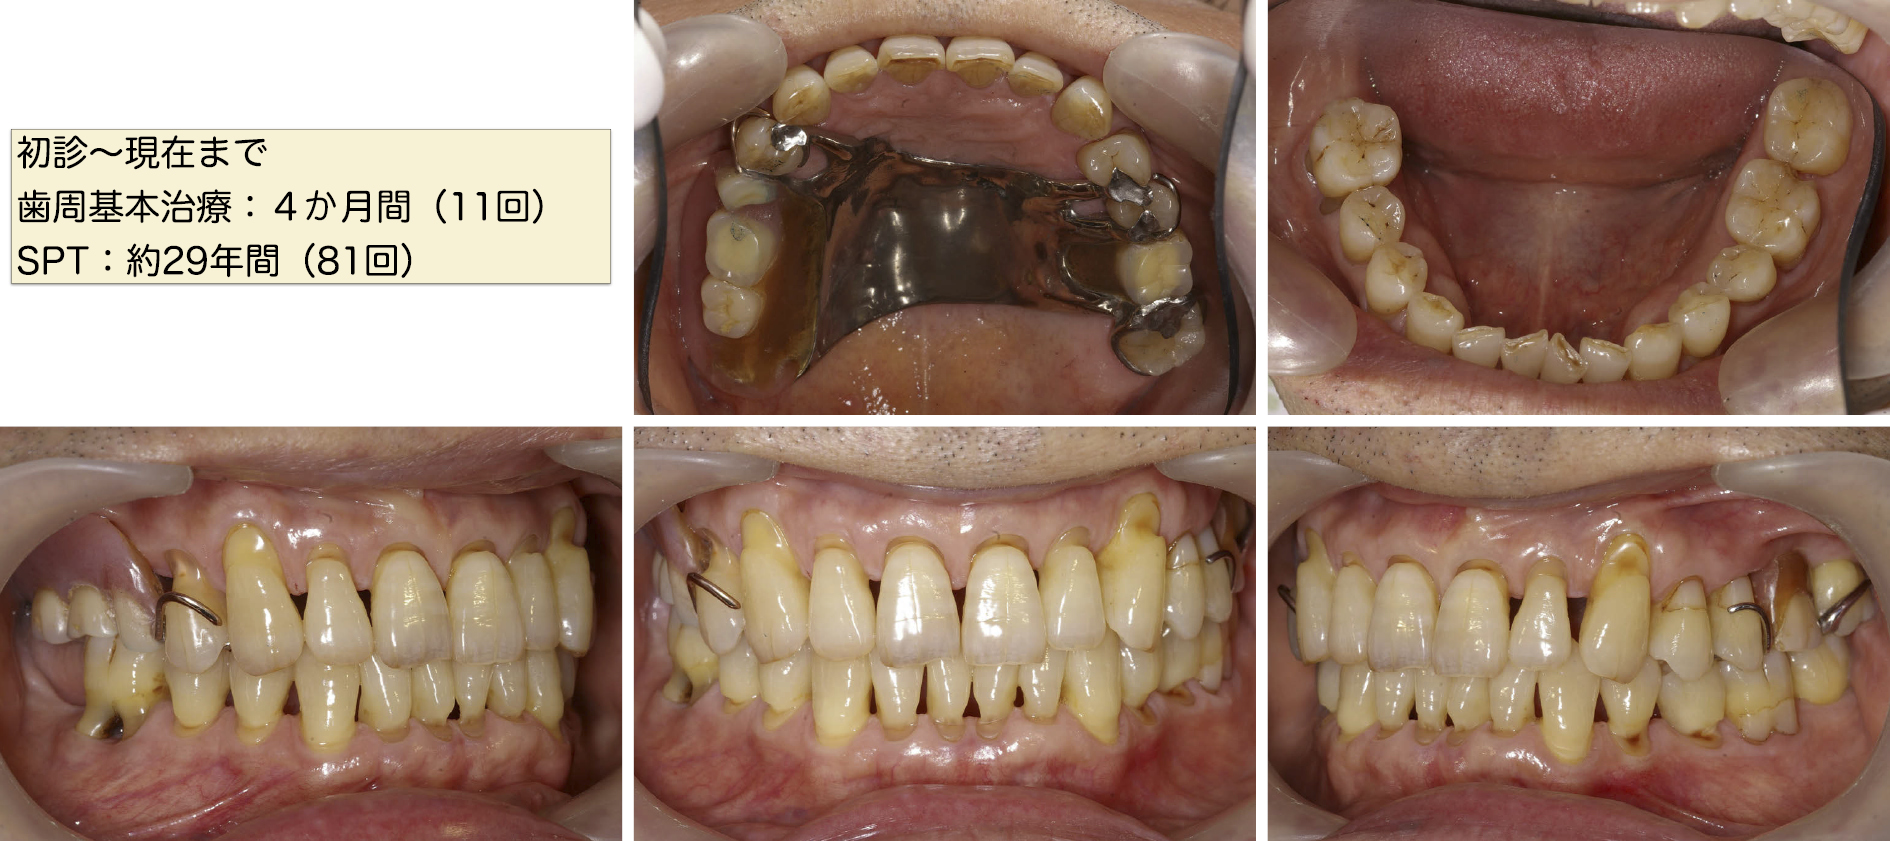

現在初診より30年が経過したが平均PPD 2.2 mm.BOP 3.5%.PCR 8.7%で症状は非常に安定している。

歯頸部に楔状欠損が見られるがこれは時としてナイトガードを未装着のまま就寝することがあることが一因と考えられる。

エックス線写真でもSPT移行時と比較して顕著な歯周病の進行は認められない(図9~101111)。

SPT中の口腔内写真 術後29年 2021年2月

SPT中のエックス線写真 術後29年 2021年2月

最新SPT中の歯周組織検査 術後29年 2021年2月